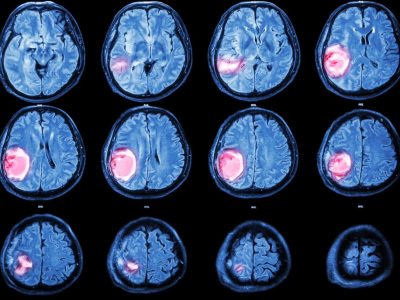

Clasificación rápida de tumores del sistema nervioso con secuenciación de lecturas largas